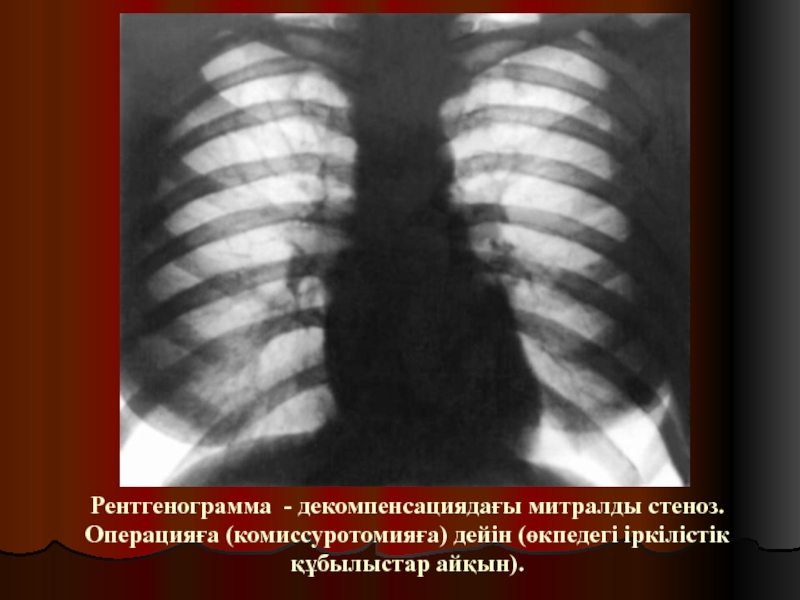

Слайд 32Рентгенограмма - декомпенсациядағы митралды стеноз. Операцияға (комиссуротомияға) дейін (өкпедегі іркілістік

құбылыстар айқын).

Рентгенограмма - декомпенсациядағы митралды стеноз. Операцияға (комиссуротомияға) дейін (өкпедегі іркілістік құбылыстар айқын).